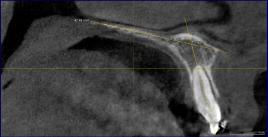

The CBCT scan was taken using a Sidexis XG 2.6.3 machine (2016 Sirona Dental Systems, GmbH) whose specifications were 90 kV, 9 to 12 mA, 8 to 14-sec exposure time, 200 μm voxel resolution and a 80 × 80 mm field of view. The patient’s head was positioned in the CBCT machine such that the sagittal plane lay along the patient’s midline and the Frankfurt horizontal plane from the upper border of the tragus of the ear to the infra-orbital rim was positioned parallel to the floor. The DICOM images of the maxilla along with the dentition were viewed using Galileos software 1.9 (Sirona Dental Systems, GmbH). The maxillary central incisor was evaluated on the tangential window of the implant-aligned view. The same images could also be viewed on the cross-sectional window of the panoramic view. However, the tangential window of the implant-aligned view provided a greater area of view compared to the cross-sectional window of the panoramic view. The DICOM images of the maxillary central incisor were sequentially viewed from the right to the left side. As the different slices were viewed, the entire length of the maxillary central incisor along with the palatal plane was visible in only one or two images. The definitive image was therefore selected. The palatal plane was drawn between the anterior and posterior limit of the palate and the long axis of the incisor was drawn to the palatal plane. The angle formed between the long axis of the maxillary tooth and the palatal plane was measured individually on each side to determine the axial inclination of each central incisor (Figure 1).

Shows the measurement of the axial inclination of the maxillary central incisor using the palatal plane as reference on the CBCT scan.